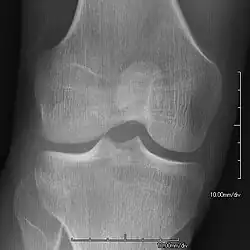

- Patellar involvement is present in approximately 75% of patients;[5] however, patellar aplasia occurs in only 20%.

- In instances in which the patellae are smaller or luxated, the knees may be unstable.

- The knee joint may appear square.

The hallmark features of this syndrome are poorly developed fingernails (especially of thumbs) - in approximately 95 percent of patients, rarely - toenails (especially the smallest nail of feet), and hypoplastic or aplastic patellae (kneecaps) - in approximately 75 percent of patients. Sometimes, this disease causes the affected person to have either no thumbnails or a small piece of a thumbnail on the edge of the thumb. The lack of development or complete absence of fingernails results from the loss of function mutations in the LMX1B gene. A unique feature of this syndrome is also the triangular lunulae at the base of the fingernails - especially in NPS patients who have nails present (in healthy individuals, without NPS, lunulae are semicircular).[10] This mutation may cause a reduction in dorsalising signals, which then results in the failure to normally develop dorsal specific structures such as nails and patellae.[18] Other common abnormalities include elbow deformities, kidney disease,[19] and abnormally shaped pelvic (hip) bones. Individual cases of this syndrome may be diverse and not fully symptomatic, as is the case with any genetic syndrome, they may also affect fitness and functioning of the body to varying degrees - from severe to mild cases (different mutations - pathogenic variants regarding other fragments/exons of the same gene and varying degrees of impact on the phenotype and areas of the body, even in the case of the same mutation in relatives in the same family).